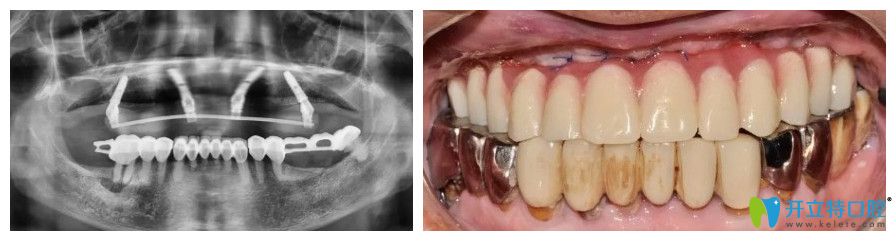

張大爺,69歲

牙齒情況:上半口牙齒脫落

種植方式:微創(chuàng)即刻種植技術(shù)

諾德齒科半口種植牙案例圖